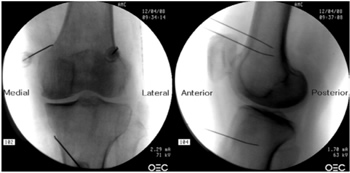

Para realizar una RFTNG guiados por fluoroscopia necesitamos una visión anteroposterior (AP) y lateral de la rodilla (Figura 2). Primero ubicamos al paciente en posición supina con una almohada debajo de la fosa poplítea (para que esté más cómodo) (16). Después de realizar asepsia y antisepsia de la rodilla, procedemos a ubicar los NG (Tabla II). El NGSL se encuentra avanzando la aguja de RFT hacia la confluencia de la diáfisis femoral lateral con el cóndilo femoral lateral en una visión AP y en un punto medio del fémur en una visión lateral. El NGSM se localiza avanzando la aguja hacia la confluencia de la diáfisis femoral medial con el cóndilo femoral medial en una visión AP y en un punto medio del fémur en una visión lateral. Por último, el NGIM se localiza avanzando la aguja hacia la confluencia de la diáfisis tibial medial con el epicóndilo tibial en una visión AP y en un punto medio de la tibia en una visión lateral (16,17).

Fig. 2. Proyección AP y lateral donde se observan las dianas terapéuticas usando fluoroscopia. Imagen tomada del artículo de Choi y cols. (9). Reproducido con la autorización de Jin Woo Shin.

Tabla II. Localización de los nervios geniculados guiados por fluoroscopia

Es muy importante tener una buena visión AP y lateral. En la proyección AP, la articulación tibiofemoral debe tener una anchura similar a ambos lados de la rodilla con el interespacio abierto (9). En la proyección lateral, debe existir una correcta superposición de ambos cóndilos femorales para realizar un bloqueo satisfactorio de los NGSM y NGSL (18).